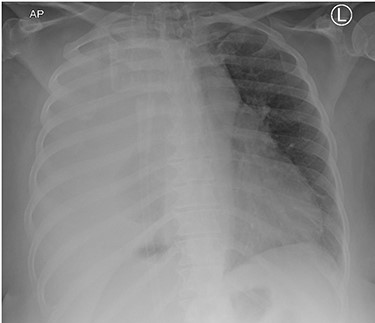

This is the case of a healthy 54-year-old female with a 3 month history of worsening dyspnea on exertion, nonproductive cough, general malaise and arthritic symptoms of her distal joints. Also, with an associated new onset, 6-month history of clubbing of her nails. She denied smoking history, weight loss, fever or chills. On examination she was found with clubbing of her nails (see Figs 1 and 2), and absent right thoracic breath sounds. Initial Chest X-ray (CXR) revealed a right side intrathoracic mass occupying the right thoracic cavity (see Fig. 3). She underwent a Chest computerized tomography (CT) scan with intravenous contrast revealing a large heterogenous mass 19 cm × 16 cm × 15 cm without gross calcifications (See Fig. 4). Then a CT-guided core needle biopsy was performed and was consistent with a benign SFT. In view of the mass size and worsening dyspnea, mass excision was performed by a single right side thoracotomy.

Initial CXR with compressed right lung, possible mass lesion and pleural effusion.